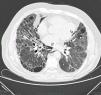

La TAC torácica de alta resolución mostró una imagen curvilínea delgada de gas en los paquetes vasculares bronquiales del lóbulo inferior derecho relacionados con el enfisema intersticial (flechas negras); también se detectaron cambios enfisematosos extensos en el mediastino próximo al corazón y la aorta torácica descendente (neumomediastino: flechas blancas).